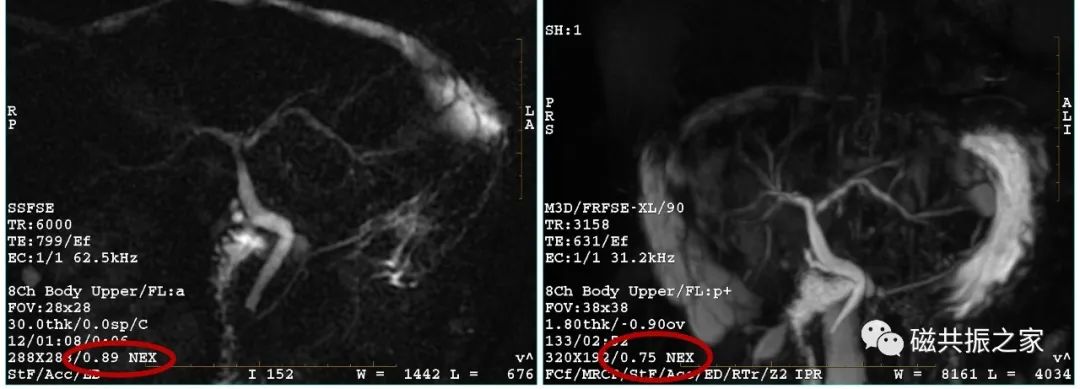

激励次数

图1,NEX为4时,扫描时间为1:52,图2,NEX为2时,扫描时间为1:05。NEX相对于其它参数来讲它们间的影响是最小的,NEX值最直接的影响的是信噪比与扫描时间,如将NEX由4改为2后,相对信噪比由图1的100% 变了图2的71%。

NEX一般设置是≥1的,但也有例外的,如采用相位部分傅里叶采集技术时可以小于1,如上图。

在一些快成像序列或3D薄层扫描中NEX常设置小于1以缩短扫描时间。